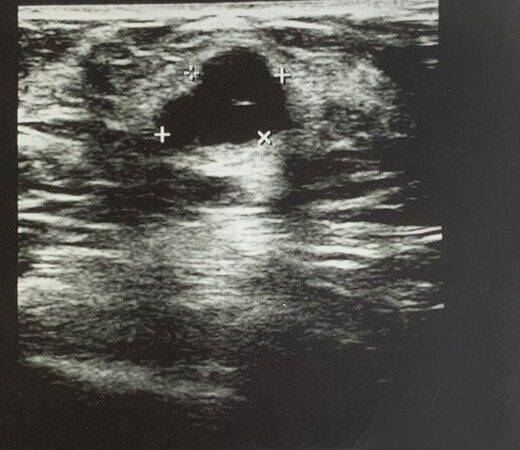

УЗИ рак груди

Фото УЗИ опухоли одной и той же пациентки с интервалом 4 месяца. Первый раз врачом УЗИ был проигнорирован неровный контур опухоли и её большой вертикальный размер. Через 4 месяца был замечен рост образования, но снова проигнорирован вертикальный размер и неровный контур. На всех этих снимках УЗИ – рак молочной железы.